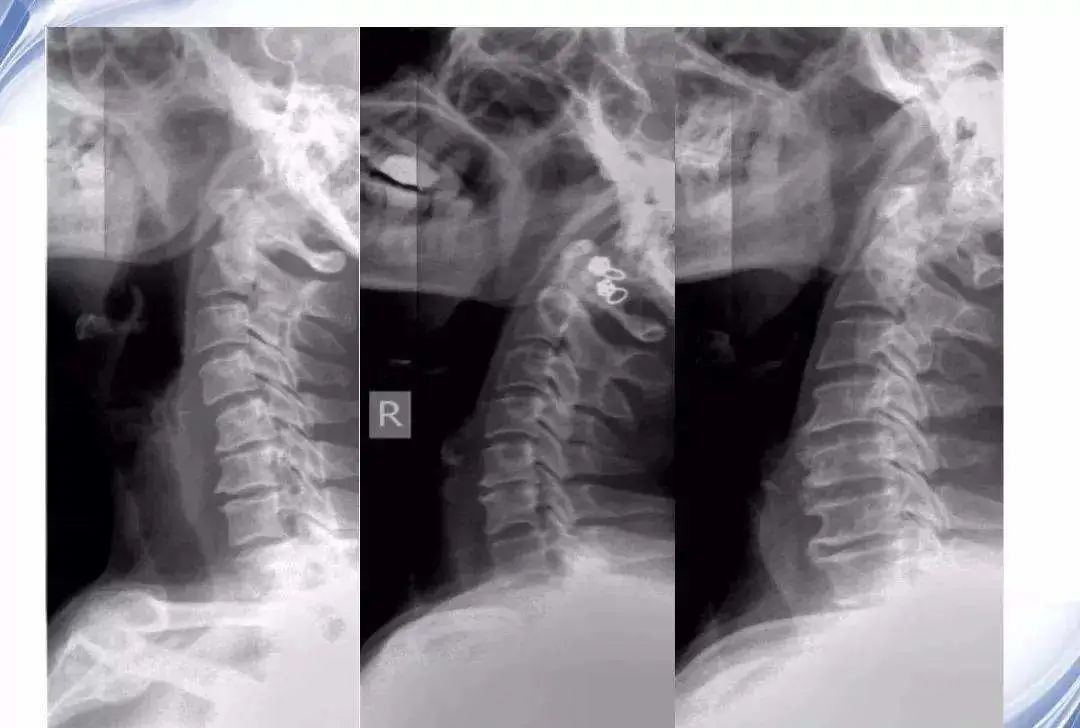

现在需要进行影像学检查,查看颈椎结构方面是否存在相关退行性改变。颈椎的影像学检查主要有两种:颈椎六位X线片检查和颈椎核磁共振检查。两者各有侧重,一般先查X线片,如果病情需要还要查核磁共振。我先为这位患者拍摄了颈椎X线片,包括六个体位X线下的颈椎投影片子,主要是查颈椎正位和侧位上有没有曲度异常,当患者仰头和低头时颈椎椎体间有没有不稳定的情况存在,以及双斜位上查看颈椎两侧神经根出口的大小及形状。该患者颈椎曲度正常,颈椎椎体稳定,双侧的神经根出口处没有狭窄,基本上是正常的颈椎影像。根据颈椎X线片,我认为该患者不能诊断为神经根型颈椎病。

(网络配图,非该患者的X线片)